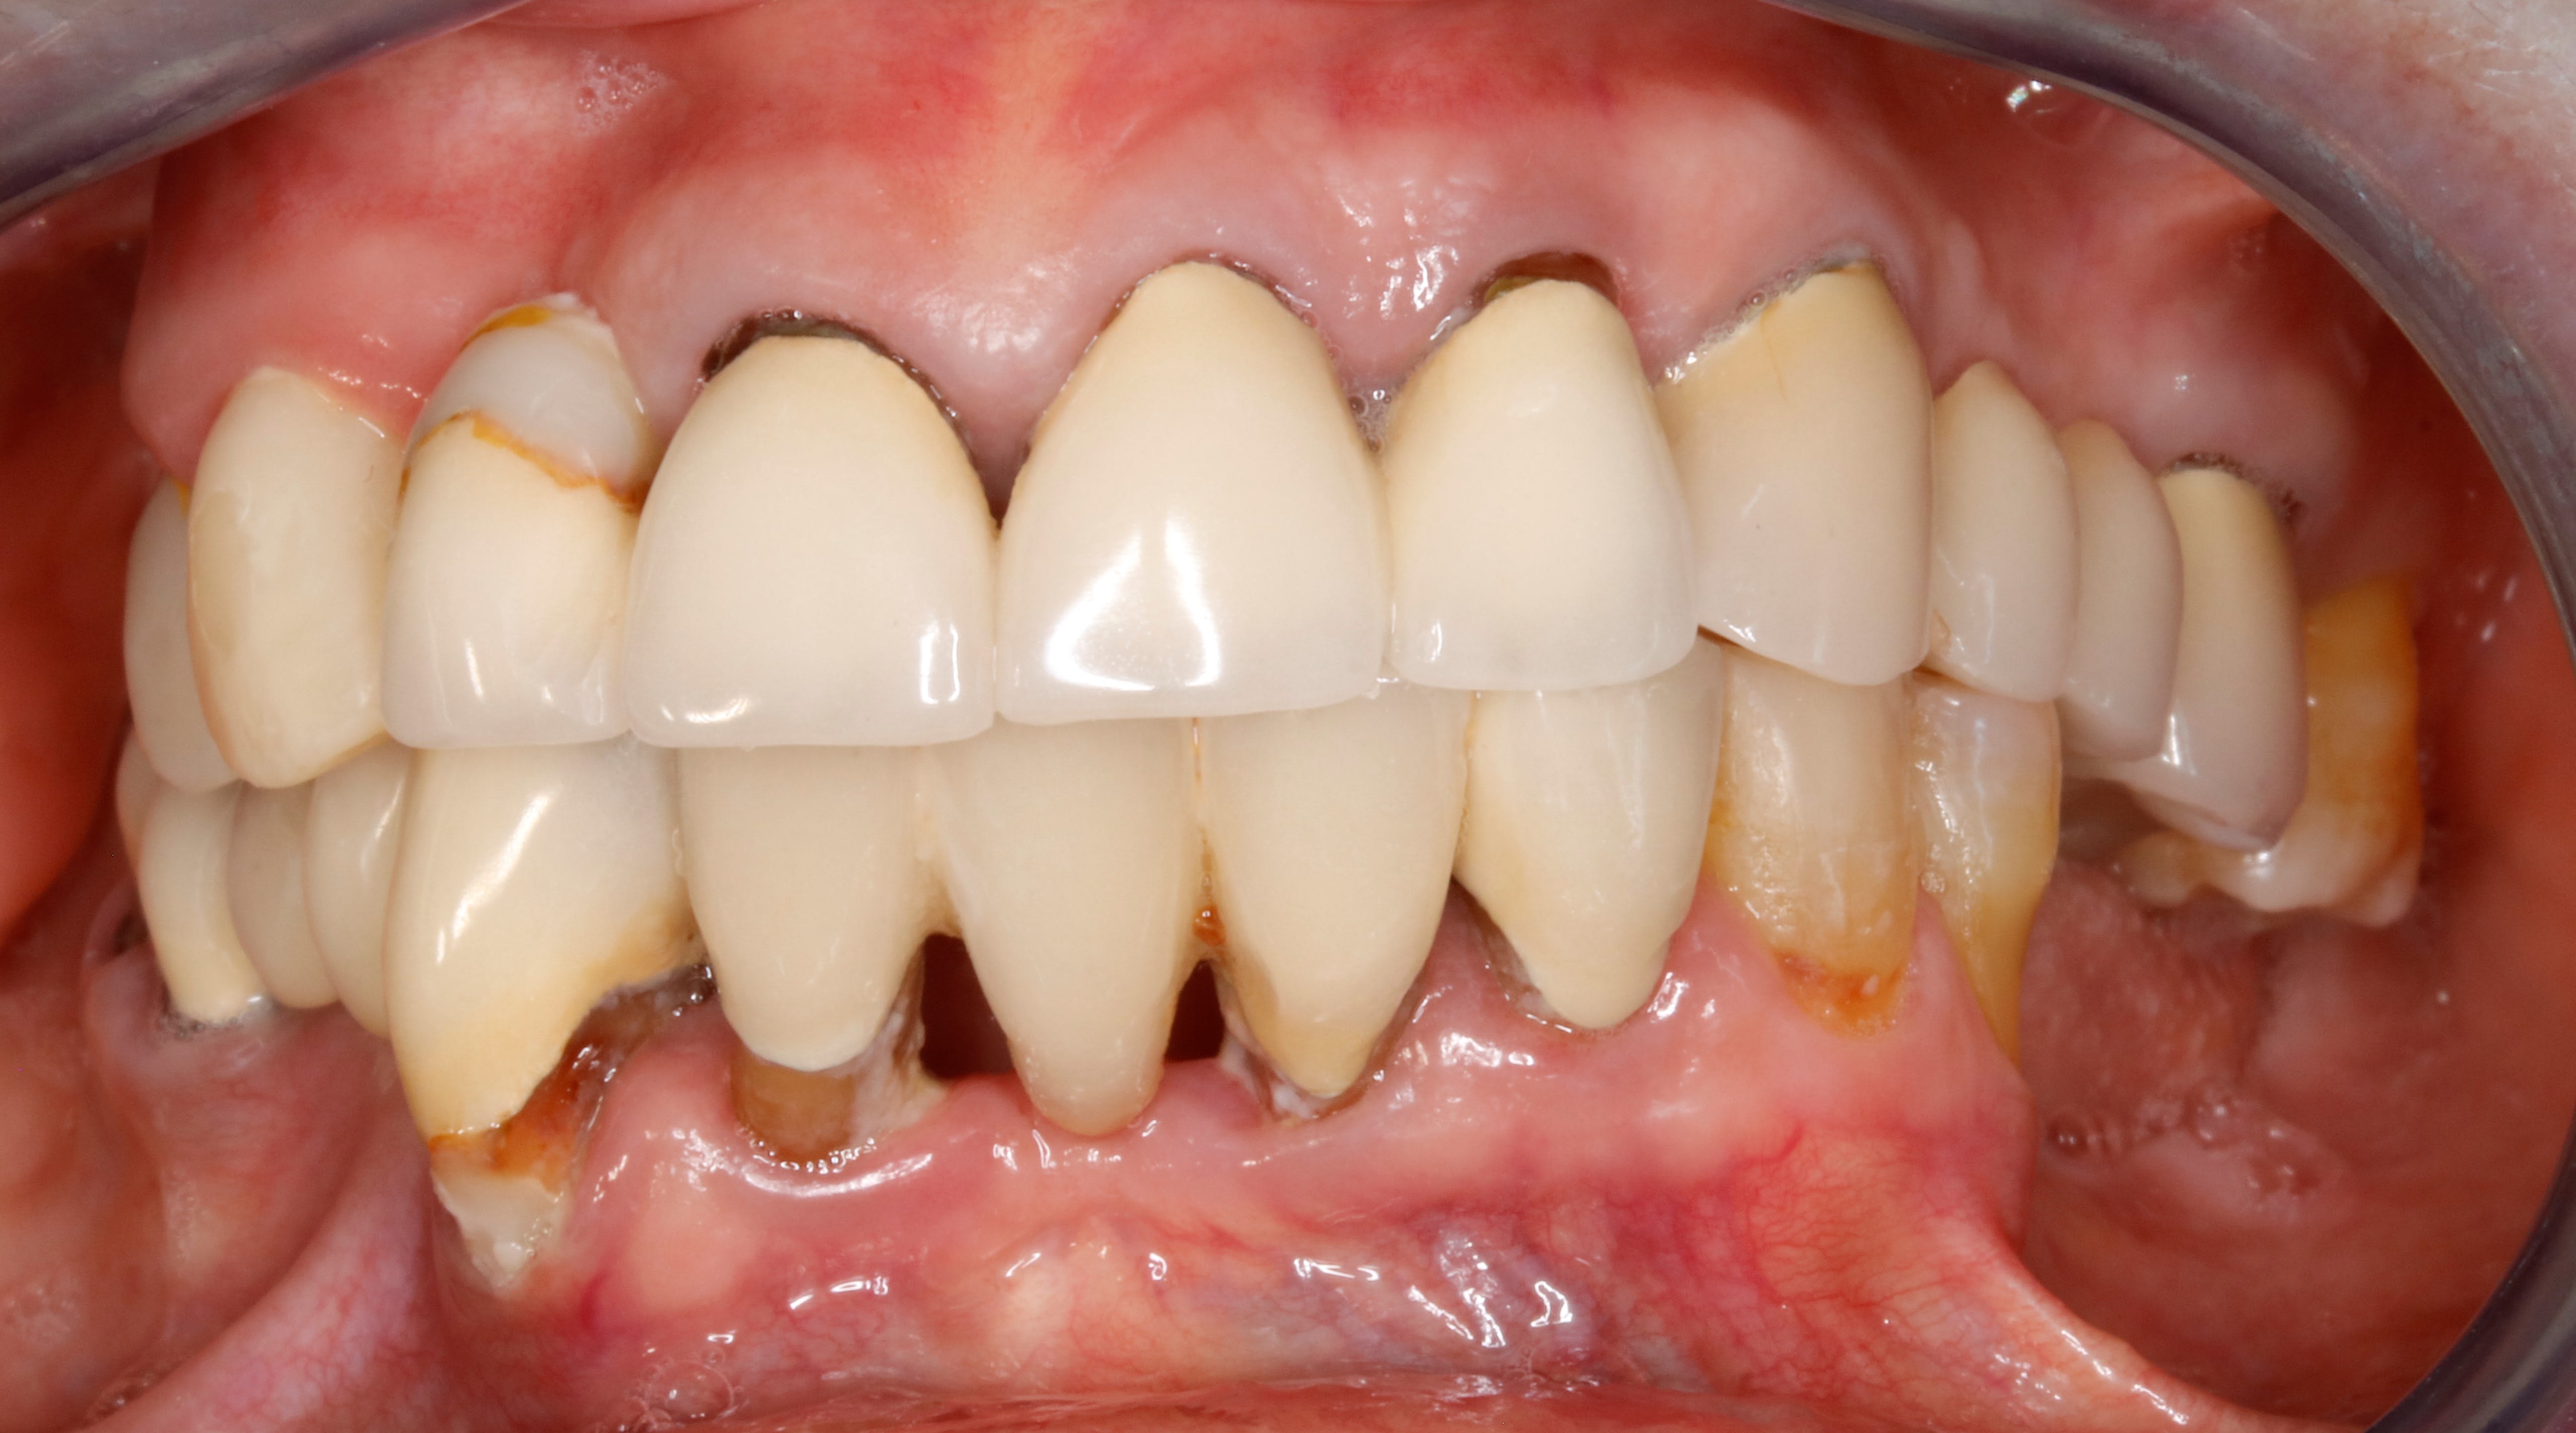

Avec des couronnes toutes neuves et des dents toutes usées autour ?

oui Posit , c est un peu l évolution du style moderne de la dentisterie .